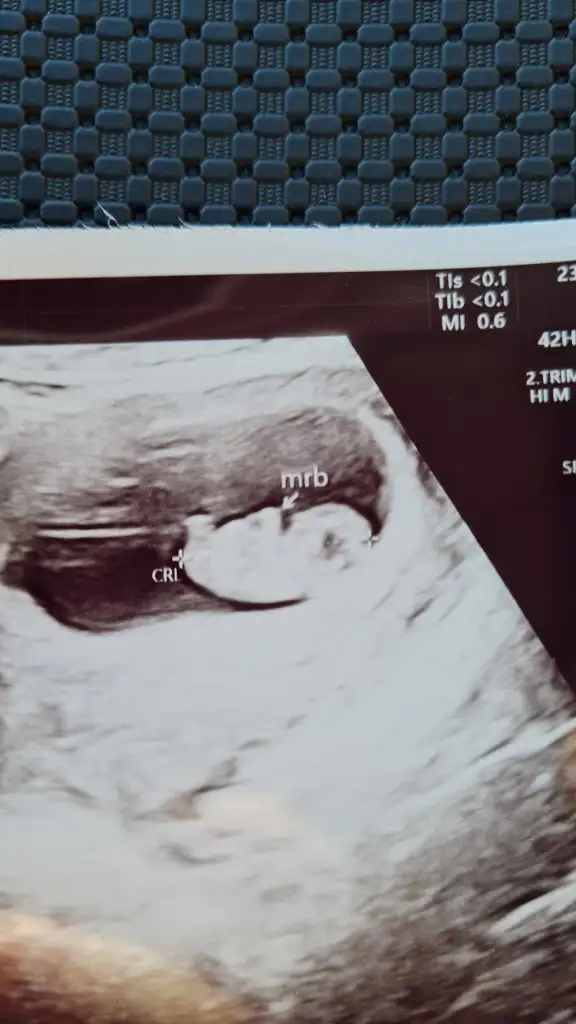

Canım nub a göre cinsel organı oluşturan yapı yatıksa kız deniliyor, senin minnoşun da yatık gibi ama alnı da erkek gibi😊 nub bilmesem erkek derdim.